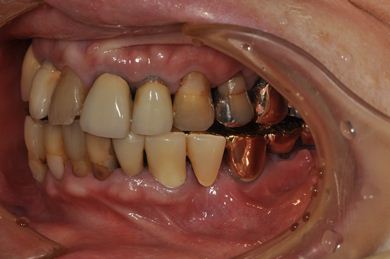

抜歯即日スピードインプラント治療+インプラント除去+セラミック治療

| 性別/年齢 | 女性 / 76歳 | ||||||||||||||||||||||||||||||||

| 主訴 | 20年前に入れたインプラントの周囲が腫れて気になっている。左下の一部治療後の歯が欠けている。 | ||||||||||||||||||||||||||||||||

| 治療内容 | インプラント5本(抜歯即日スピードインプラント)、ハイブリッドセラミック9本(セラミック用土台2本)、メタルボンドセラミック2本(メタルボンド用土台1本)、インプラント除去1本 | ||||||||||||||||||||||||||||||||